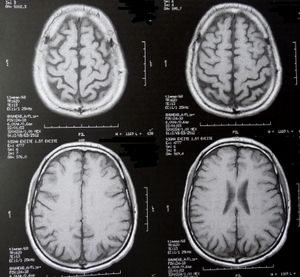

Sie sind hier: Startseite Berichte Gesundheit Mädchen: Verhaltensstörung im Gehirn nachweisbar Gehirnscans: machen Verhaltensstörungen sichtbar. Bild: pixelio.de, D. Schütz

Gehirnscans: machen Verhaltensstörungen sichtbar. Bild: pixelio.de, D. Schütz